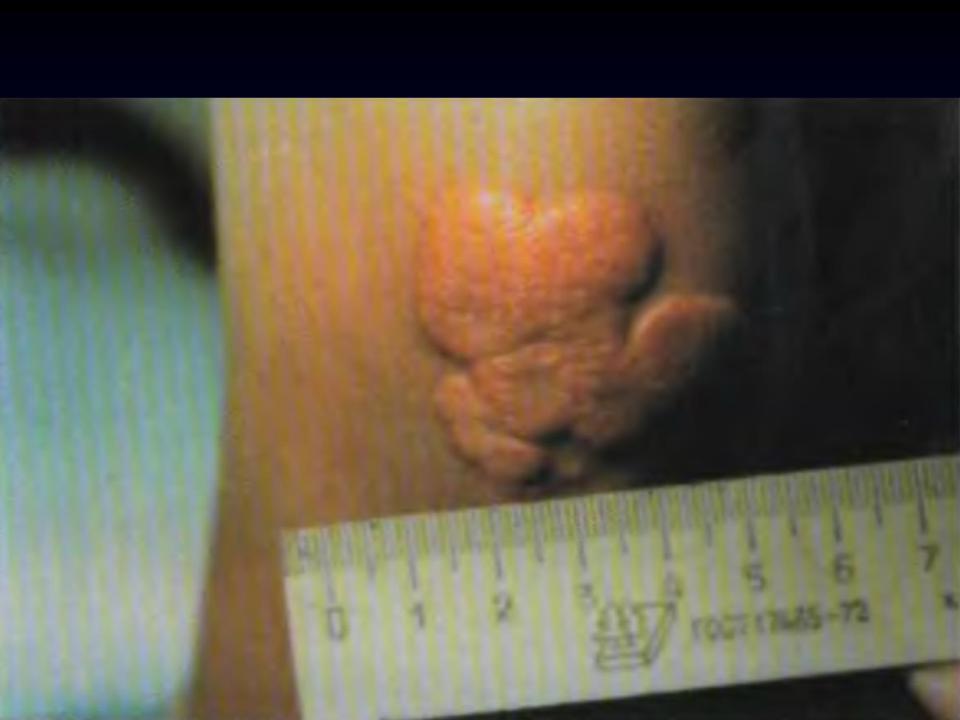

-xanthomas (lumpy formations in the area of ​​joints, Achilles tendons, caused by the deposition of cholesterol);

Tuberous xanthomas of the extensor surface of

the elbows: